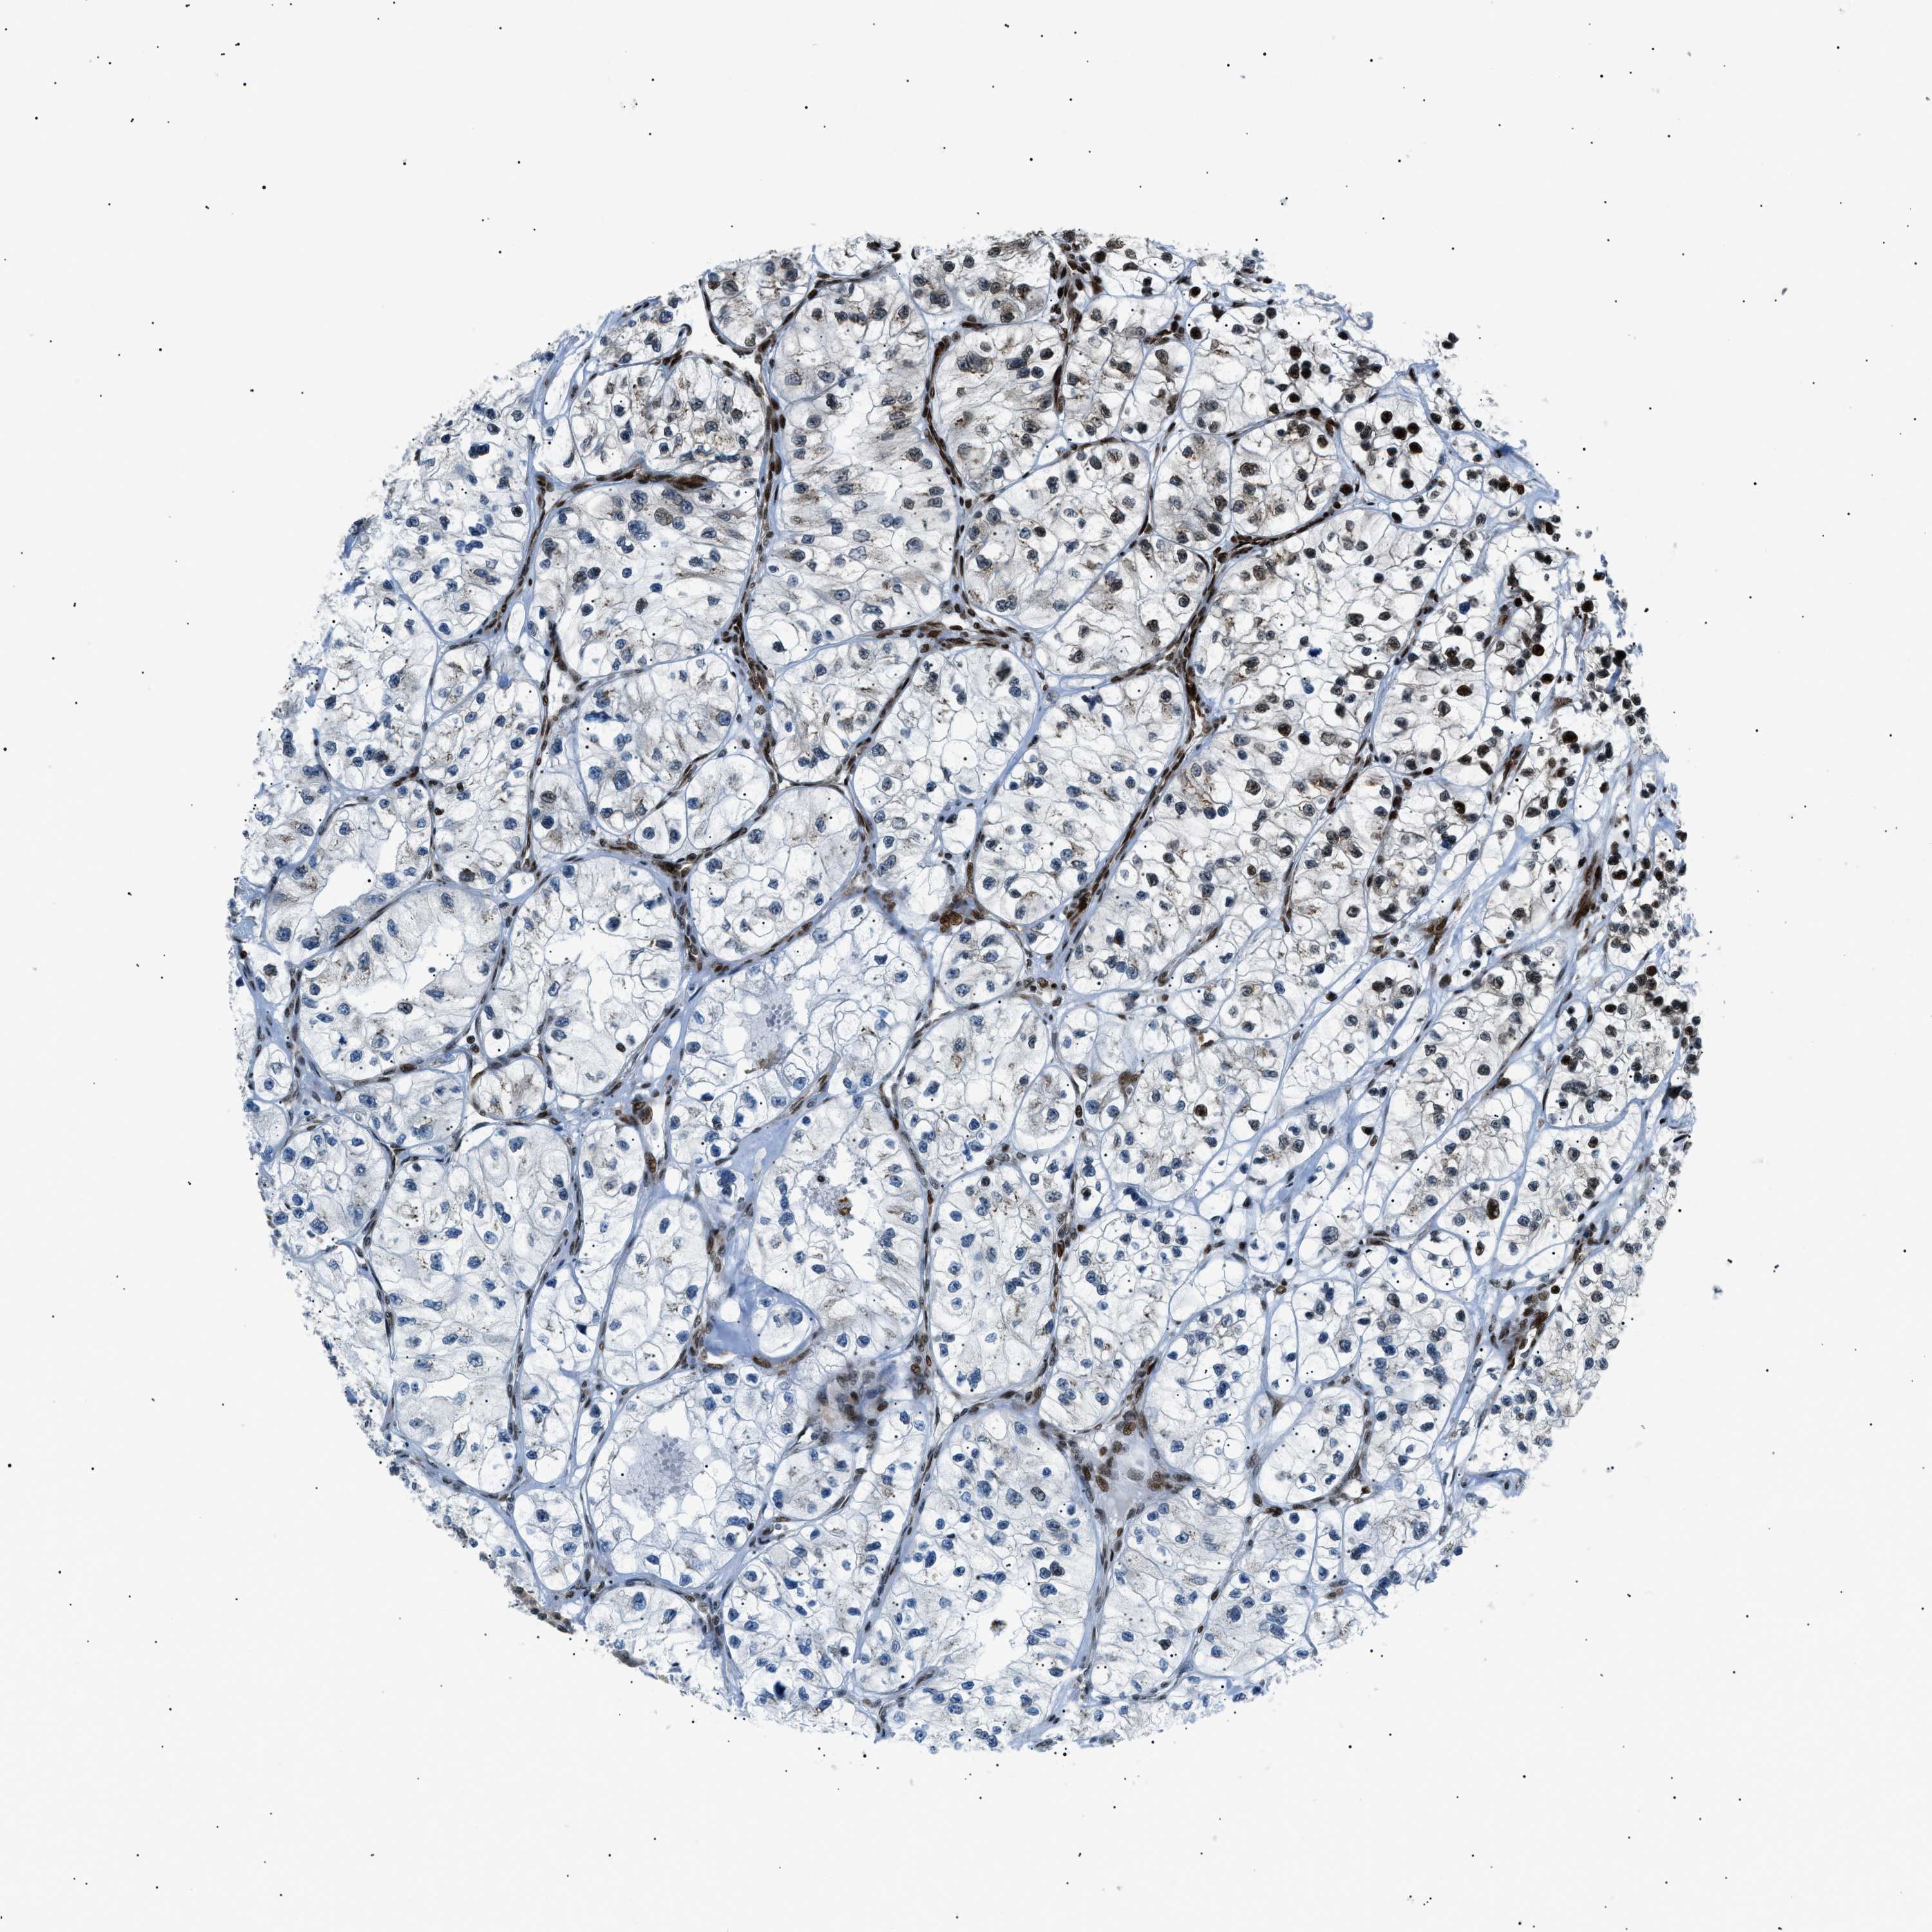

HNRNPK is validated prognostic, high expression is favorable in Kidney Renal Clear Cell Carcinoma (TCGA)

Best expression cut offi

Based on the FPKM value of each gene, patients were classified into two groups and association between prognosis (survival) and gene expression (FPKM) was examined. The best expression cut-off refers the FPKM value that yields maximal difference with regard to survival between the two groups at the lowest log-rank P-value. Best expression cut-off was selected based on survival analysis .

When clicking on this number, the vertical dashed line indicating cut-off, the interactive survival plot, and the Kaplan-Meier curve will be adjusted to show results based on the best expression cut-off.

: 263.23

P scorei

Log-rank P value for Kaplan-Meier plot showing results from analysis of correlation between mRNA expression level and patient survival.

N/A

5-year survival highi

5-year survival for patients with higher expression than the expression cutoff.

For melanoma and glioma, 3-year survival is shown.

5-year survival lowi

5-year survival for patients with lower expression than the expression cutoff.

Average pTPM 336.9

Number of samples 521